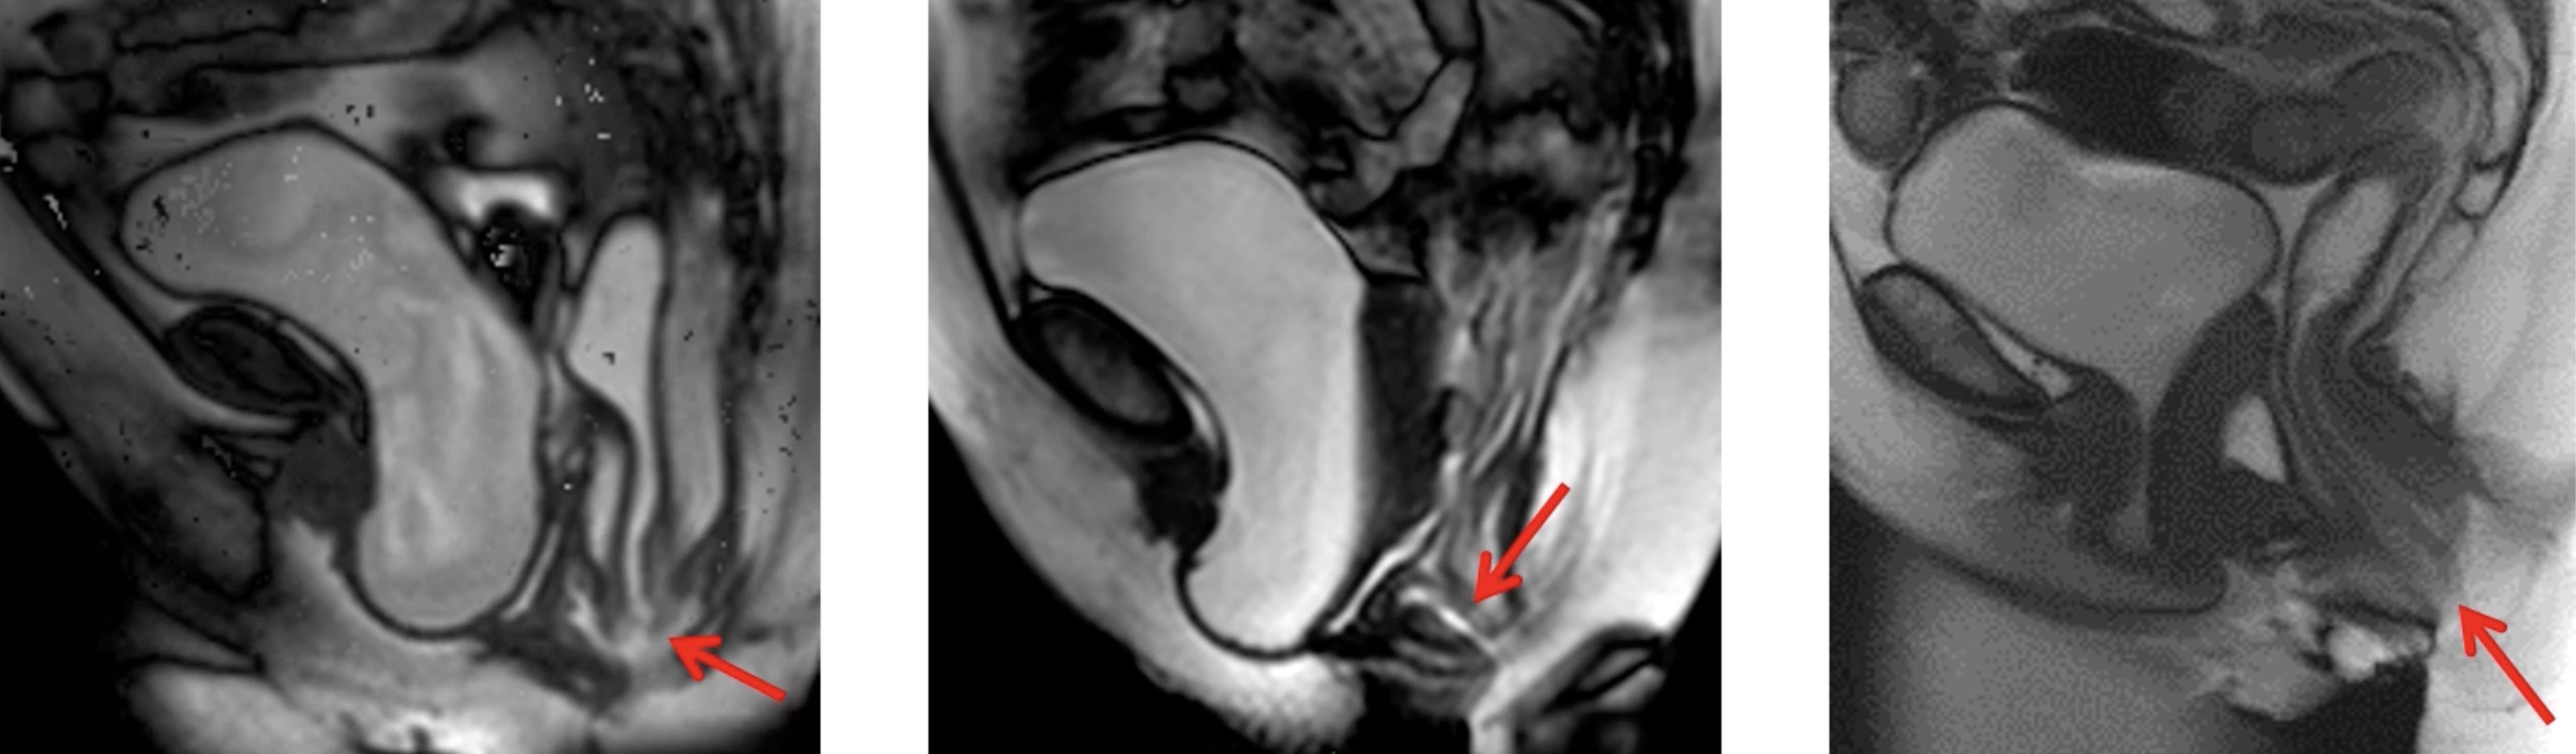

Rectocèle antérieure = rétentionniste ?

significative si > 2 cm de profondeur

significative si > 2 cm de profondeur

Prolapsus rectal (intussusception) = obstructif ?

2 = affleure le canal anal, 3 = intra-anal, 4 = extériorisé

2 = affleure le canal anal, 3 = intra-anal, 4 = extériorisé

→ même gradation pour les péritonéocèles rectales

Complications

- dilatation des uretères

- allongement hypertrophique lèvre antérieure col (> 3 cm)

- ulcère solitaire du rectum (pseudopolypoïde face antérieure)